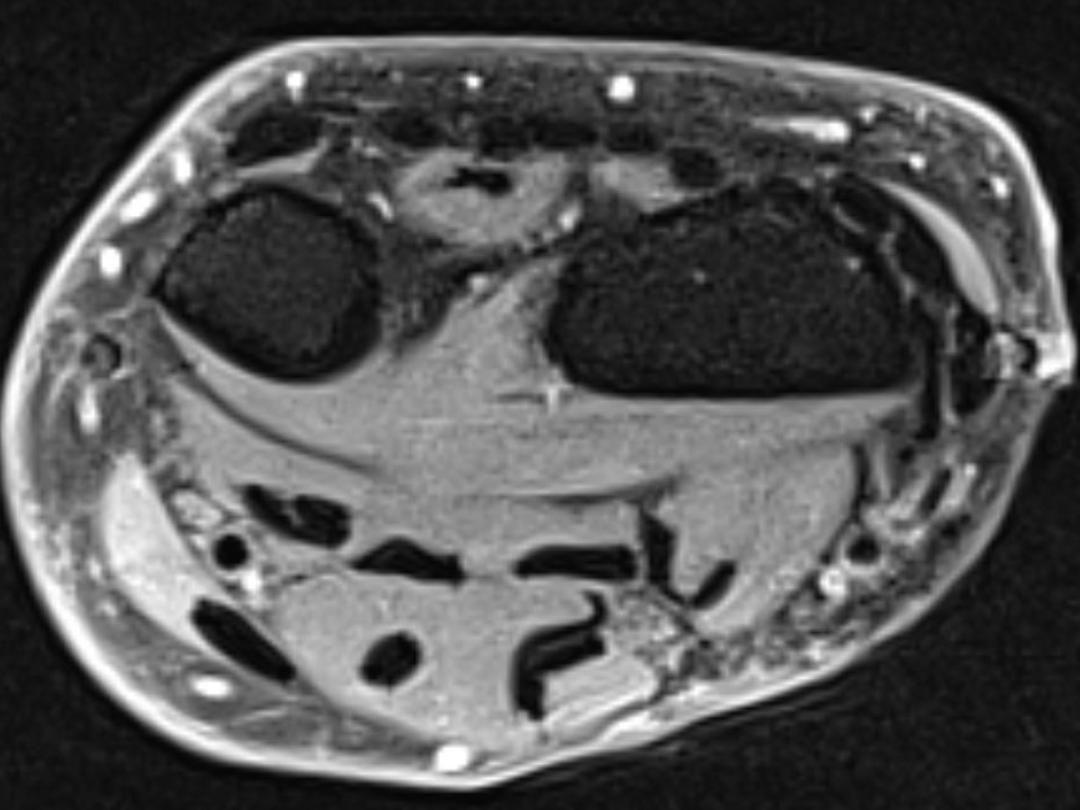

Bij een 62-jarige patiënte werd een ganglioncyste aan de volaire zijde van de linker pols geaspireerd en geïnfiltreerd met corticosteroïden. Volgens de richtlijnen is hiervoor geen indicatie. Enkele weken hierna presenteerde de patiënte zich met hevige pijnklachten en functieverlies van de pols zonder paresthesieën. Wij stelden vast dat het een ruptuur van de pees van de m. flexor carpi radialis (FCR) betrof. De patiënte werd behandeld met pijnstilling en een brace. Bij controle was er minimaal functieverlies van de pols.

Bij corticosteroïdinfiltratie van een volair ganglion ter hoogte van de FCR is enige terughoudendheid geboden. Aspiratie, gecombineerd met infiltratie van corticosteroïden, wordt afgeraden bij patiënten met artrose van het scafotrapeziotrapezoïdale gewricht en het carpometacarpale gewricht van de duim vanwege de kans op een FCR-peesruptuur.